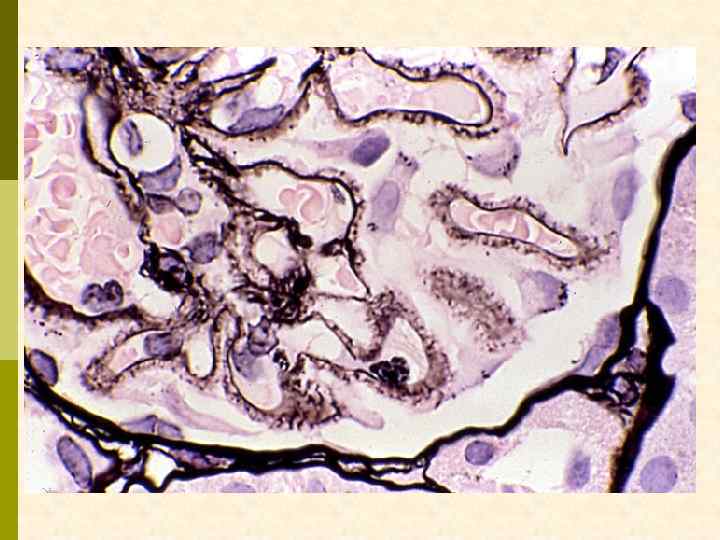

Анти-ГБМ иммунофлуоресценция обнаруживает зернистые депозиты вдоль ГБМ. Дискретная природа депозитов хорошо видна на тангенциальных срезах ГБМ.

При серебрении хорошо выявляются исходящие из ГБМ кнаружи отростки, располагающиеся между иммунными депозитами.